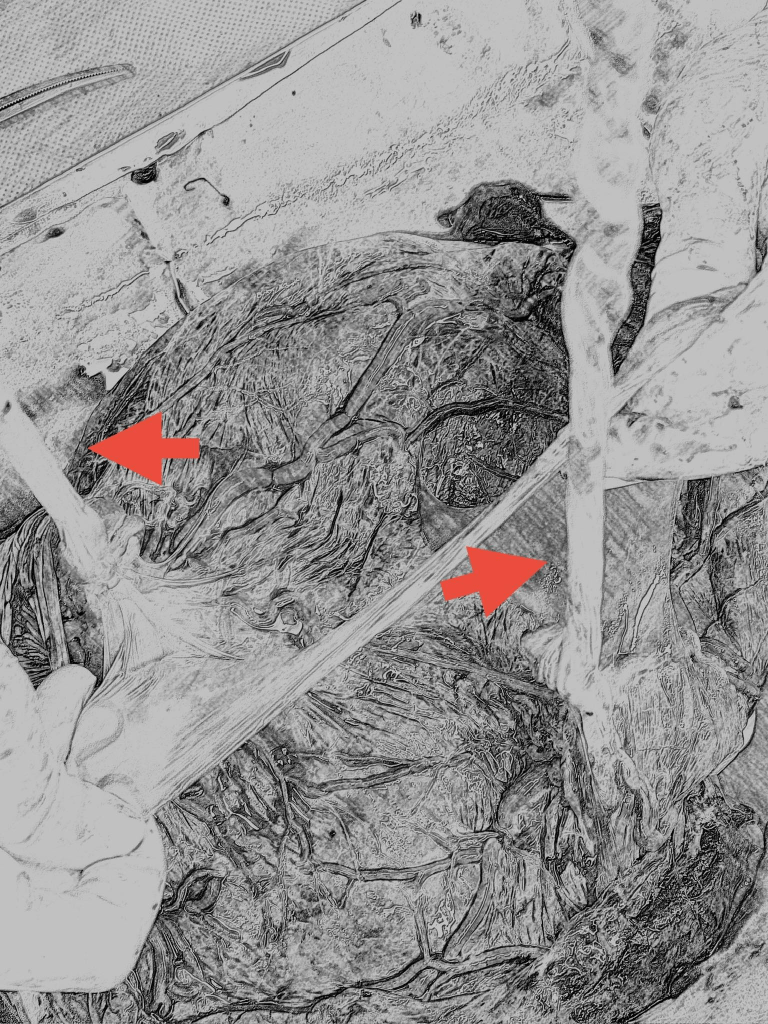

文章中的是經過轉化的手繪圖

實際的照片為了避免因為血腥而被鎖

同卵

單絨毛膜雙羊膜雙胞胎

你可以看到左右各有一個臍帶(紅色箭頭指的地方

中間就是羊膜的隔間